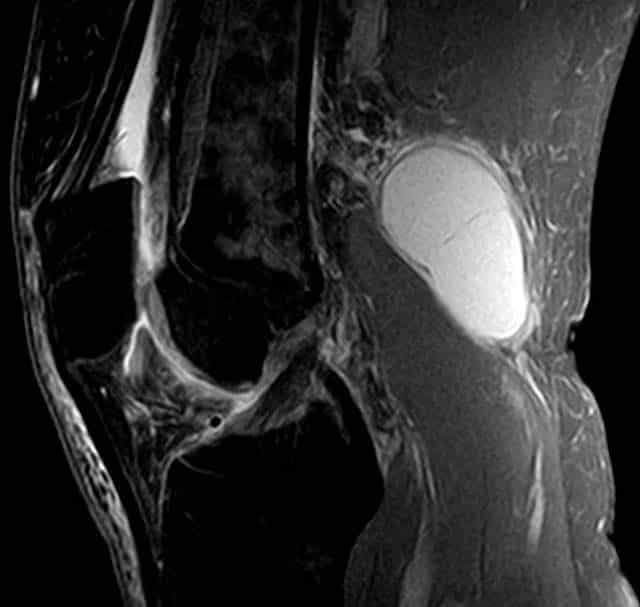

The popliteal fossa is a diamond shaped area located on the posterior aspect of the knee. It is the main path by which vessels and nerves pass between the thigh and the leg. In this article, we shall look at the anatomy of the popliteal fossa – its borders, contents and clinical correlations. Borders The popliteal fossa is diamond shaped with four borders. These borders are formed by the muscles in the posterior compartment of the leg and thigh: Superomedial – semimembranosus. Superolateral – biceps femoris. Inferomedial – medial head of the gastrocnemius. Inferolateral – lateral head of the gastrocnemius and plantaris. The floor of the popliteal fossa is formed by the posterior surface of the knee joint capsule, popliteus muscle and posterior femur. The roof is made of up two layers: popliteal fascia and skin. The popliteal fascia is continuous with the fascia lata of the leg. By TeachMeSeries Ltd (2025) Fig 1The borders of the popliteal fossa are formed by the muscles of the thigh and leg. Pro Feature - 3D Model You've Discovered a Pro Feature Access our 3D Model Library Explore, cut, dissect, annotate and manipulate our 3D models to visualise anatomy in a dynamic, interactive way. Learn More Contents The popliteal fossa is the main conduit for neurovascular structures entering and leaving the leg. Its contents are (medial to lateral): Popliteal artery Popliteal vein Tibial nerve Common fibular nerve (common peroneal nerve) The tibial and common fibular nerves are the most superficial of the contents of the popliteal fossa. They are both branches of the sciatic nerve. The common fibular nerve follows the biceps femoris tendon, travelling along the lateral margin of the popliteal fossa. The small saphenous vein pierces the popliteal fascia and passes between the two heads of gastrocnemius to empty into the popliteal vein. In the popliteal fossa, the deepest structure is the popliteal artery. It is a continuation of the femoral artery, and travels into the leg to supply it with blood. By TeachMeSeries Ltd (2025) Fig 2The contents of the popliteal fossa. Clinical Relevance Swelling in the Popliteal Fossa The appearance of a mass in the popliteal fossa has many differential diagnoses. The two main causes are baker’s cyst and aneurysm of the popliteal artery. Baker’s Cyst A Baker’s cyst (popliteal cyst) refers to the inflammation and swelling of the semimembranosus bursa – a sac-like structure containing a small amount of synovial fluid. It usually arises in conjunction with osteoarthritis of the knee. Whilst it usually self-resolves, the cyst can rupture and produce symptoms similar to deep vein thrombosis. By Hellerhoff [CC-BY-SA-3.0-2.5-2.0-1.0], via Wikimedia Commons Fig 3MRI Scan of a Baker’s cyst. Popliteal Aneurysm An aneurysm is a dilation of an artery, which is greater than 50% of the normal diameter. The popliteal fascia (the roof of the popliteal fossa) is tough and non-extensible, and so an aneurysm of the popliteal artery has consequences for the other contents of the popliteal fossa. The tibial nerve is particularly susceptible to compression from the popliteal artery. The major features of tibial nerve compression are: Weakened or absent plantar flexion Paraesthesia of the foot and posterolateral leg An aneurysm of the popliteal artery can be detected by an obvious palpable pulsation in the popliteal fossa. An arterial bruit may be heard on auscultation. Other Causes Rarer causes of a popliteal mass include deep vein thrombosis, adventitial cyst of the popliteal artery and various neoplasms (such as rhabdomyosarcoma). Pro Feature - Dissection Images The borders and contents of the femoral triangle The borders and contents of the femoral triangle You've Discovered a Pro Feature Access our Dissection Image Library Enhance your understanding with high-resolution dissection images showcasing real-life anatomy. Learn More Do you think you’re ready? Take the quiz below Pro Feature - Quiz The Popliteal Fossa Question 1 of 3 Submitting... Skip Next Rate question: You scored 0% Skipped: 0/3 1800 More Questions Available Upgrade to TeachMeAnatomy Pro Challenge yourself with over 1800 multiple-choice questions to reinforce learning Learn More Rate This Article